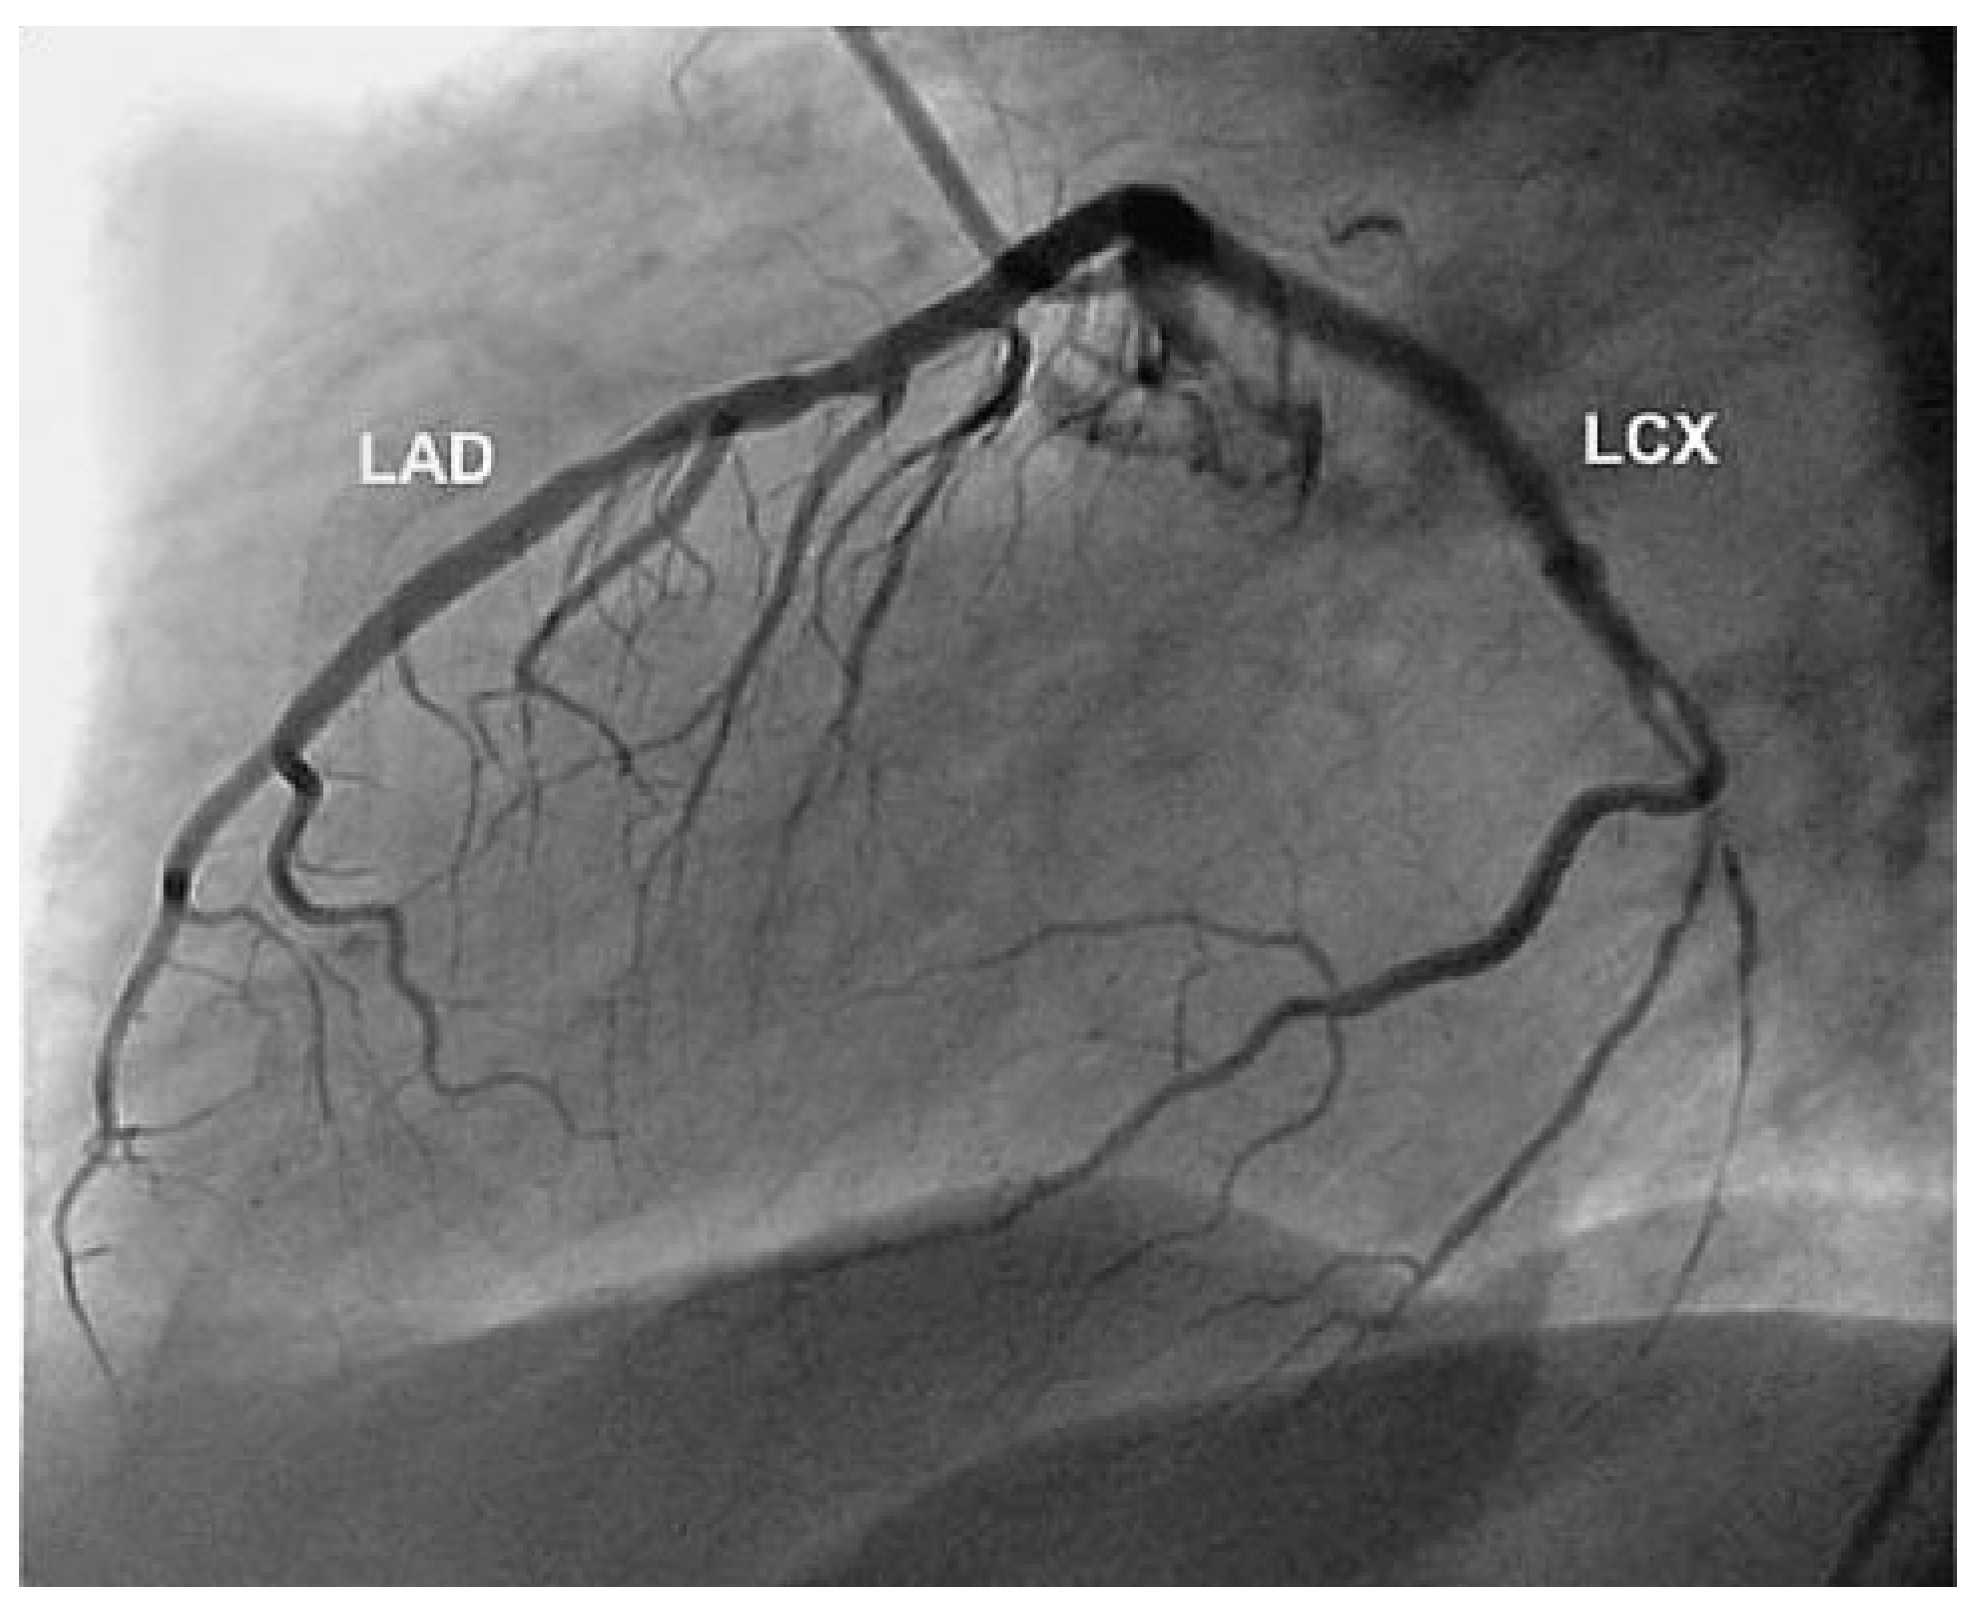

Aneurysm of the Left Circumflex Coronary Artery